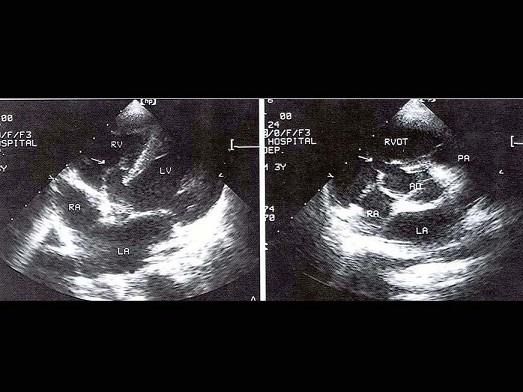

该病例最可能的诊断?(?)A.主动脉窦瘤B.室间隔缺损C.右室流出道狭窄D.室间隔膜部瘤并破裂E.以上都不是

问题 该病例最可能的诊断?(?)

选项 A.主动脉窦瘤 B.室间隔缺损 C.右室流出道狭窄 D.室间隔膜部瘤并破裂 E.以上都不是

答案 D